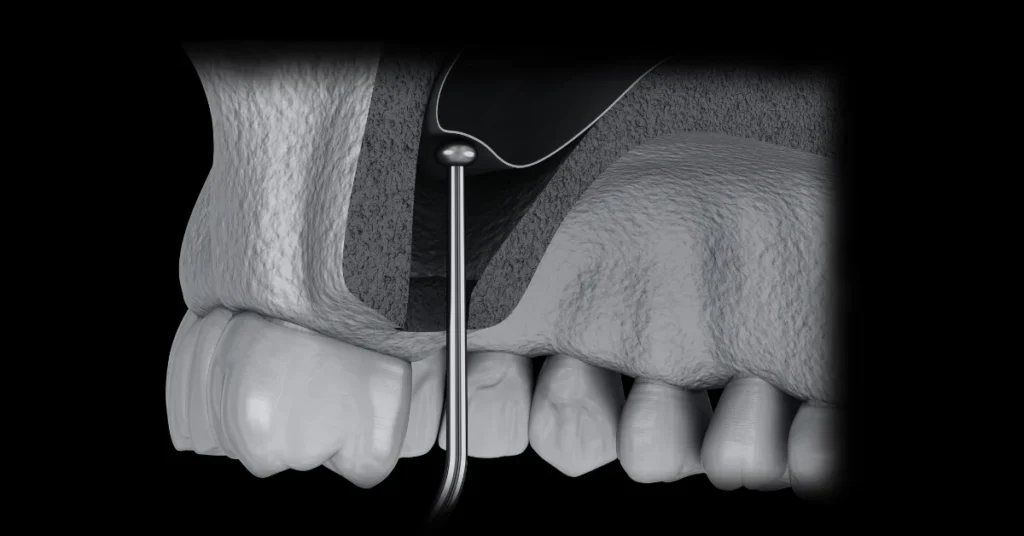

2. Procedura de inserare a implantului dentar

ETAPA 2: Procedura de Inserare a Implantului Dentar

Procedura propriu-zisa dureaza aproximativ 15-90 MINUTE, in functie de numarul de implanturi inserate si de complexitatea fiecarui caz.

Aditia de os

Sinus lift

Grefa gingivala